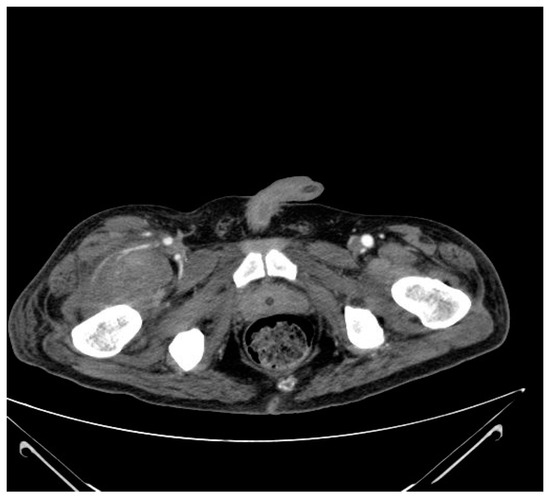

3.4. Case No. 4

| 3 | TSCI | Th1–Th2 | 0 | No | Yes | Yes | Edema of the right lower limb | Multifocal in tight, right limb |

| 4 | TSCI | C7 | 2 | Yes | No | No | Edema of the left lower limb | Gastrocnemius, left limb |